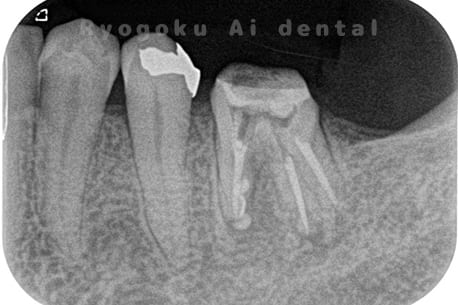

Case05

-

- 原因

- 慢性根尖性歯周炎

- 治療内容

- マイクロエンド

- 治療費用

- 121,000円(被せ物は含まない)

他院ではお薬の交換と抗生剤の処方で経過を診ていた患者さんです。歯茎の腫れが治らないとのことで、根管治療を開始し、2回目のご来院で腫れが引いたケースです。現在は被せ物も入り、良好に経過しております。

<リスク・副作用>

術後は痛み、腫れ、痺れなどの副作用が生じる場合があります。症状が再発する可能性があります。